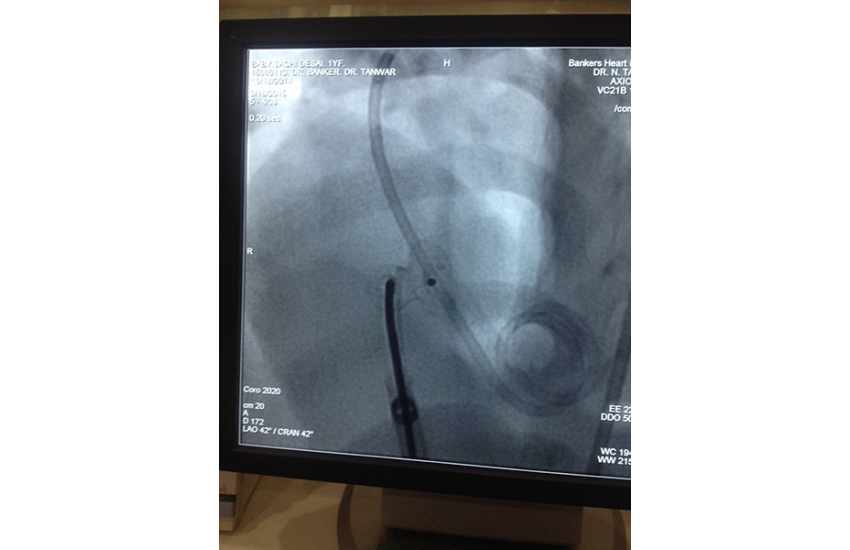

1 year girl with 7 kg weight successfully undergone Ventricular Septal Defect device closure...

18 Sep 2015